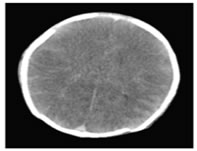

Figure 9: In a 3 month old child with history of fall from height, Axial NECT scan reveals, SAH along the bilateral fronto-parietal lobe cortical sulci.